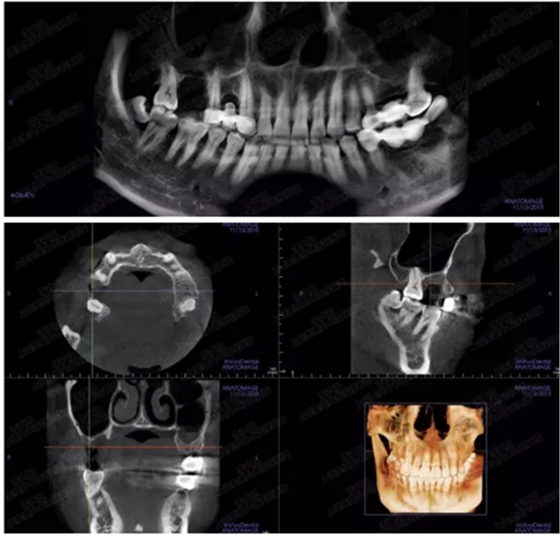

病例一

上頜竇多分隔3mm

05.png

提升8mm

06.png

07.png

修復(fù)時(shí)根尖片

08.png

09.png

口內(nèi)照片

001.png

修復(fù)后一年

002.png